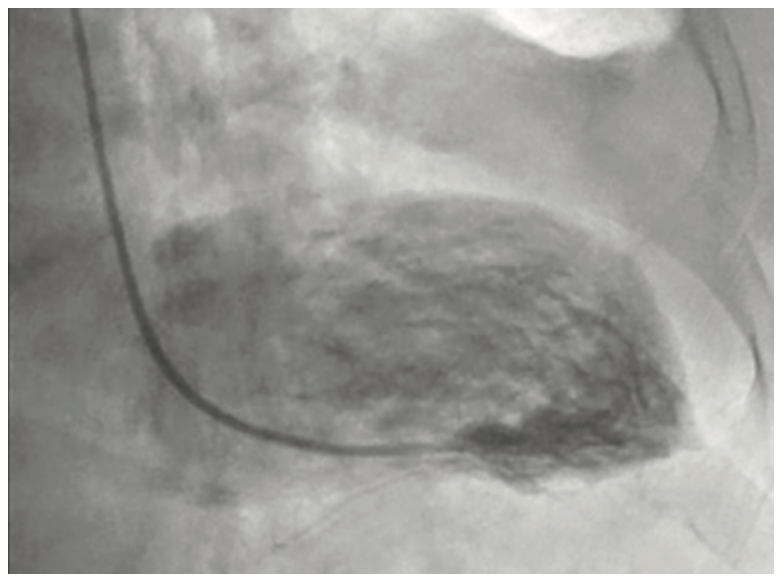

She was widowed, lived alone, and quit smoking 4 years ago, with a 40 pack-year smoking history. Her family history was non-contributory. She had noticed some dyspnea on exertion during routine chores such as mowing the lawn and carrying laundry upstairs, which she attributed to deconditioning. She was otherwise asymptomatic, even during her episode of supraventricular tachycardia (SVT) during her recent colonoscopy. During her TTE, the technologist notified the cardiologist of a 9-centimeter ascending aortic aneurysm, effacing the sinotubular junction with dilated sinuses of Valsalva. The TTE also demonstrated moderate aortic regurgitation. There was no evidence of vegetation or aortic dissection, or pericardial effusion. The patient was admitted to the University Hospital from the office for further management. A computed tomography scan of the chest with contrast was done in the emergency department to further define the aneurysm. Cardiac catheterization was performed the following day, revealing normal coronaries, normal left ventricular systolic function, and a 9-centimeter ascending aortic aneurysm. She underwent urgent cardiothoracic surgery. The surgeon repaired her aortic root with a Dacron patch and replaced her aortic valve with a bioprosthetic pericardial aortic valve. The patient had an otherwise unremarkable post-operative course, primarily consisting of blood pressure control. She was discharged with surgical follow-up within 1 week and cardiology follow-up in 2 weeks.